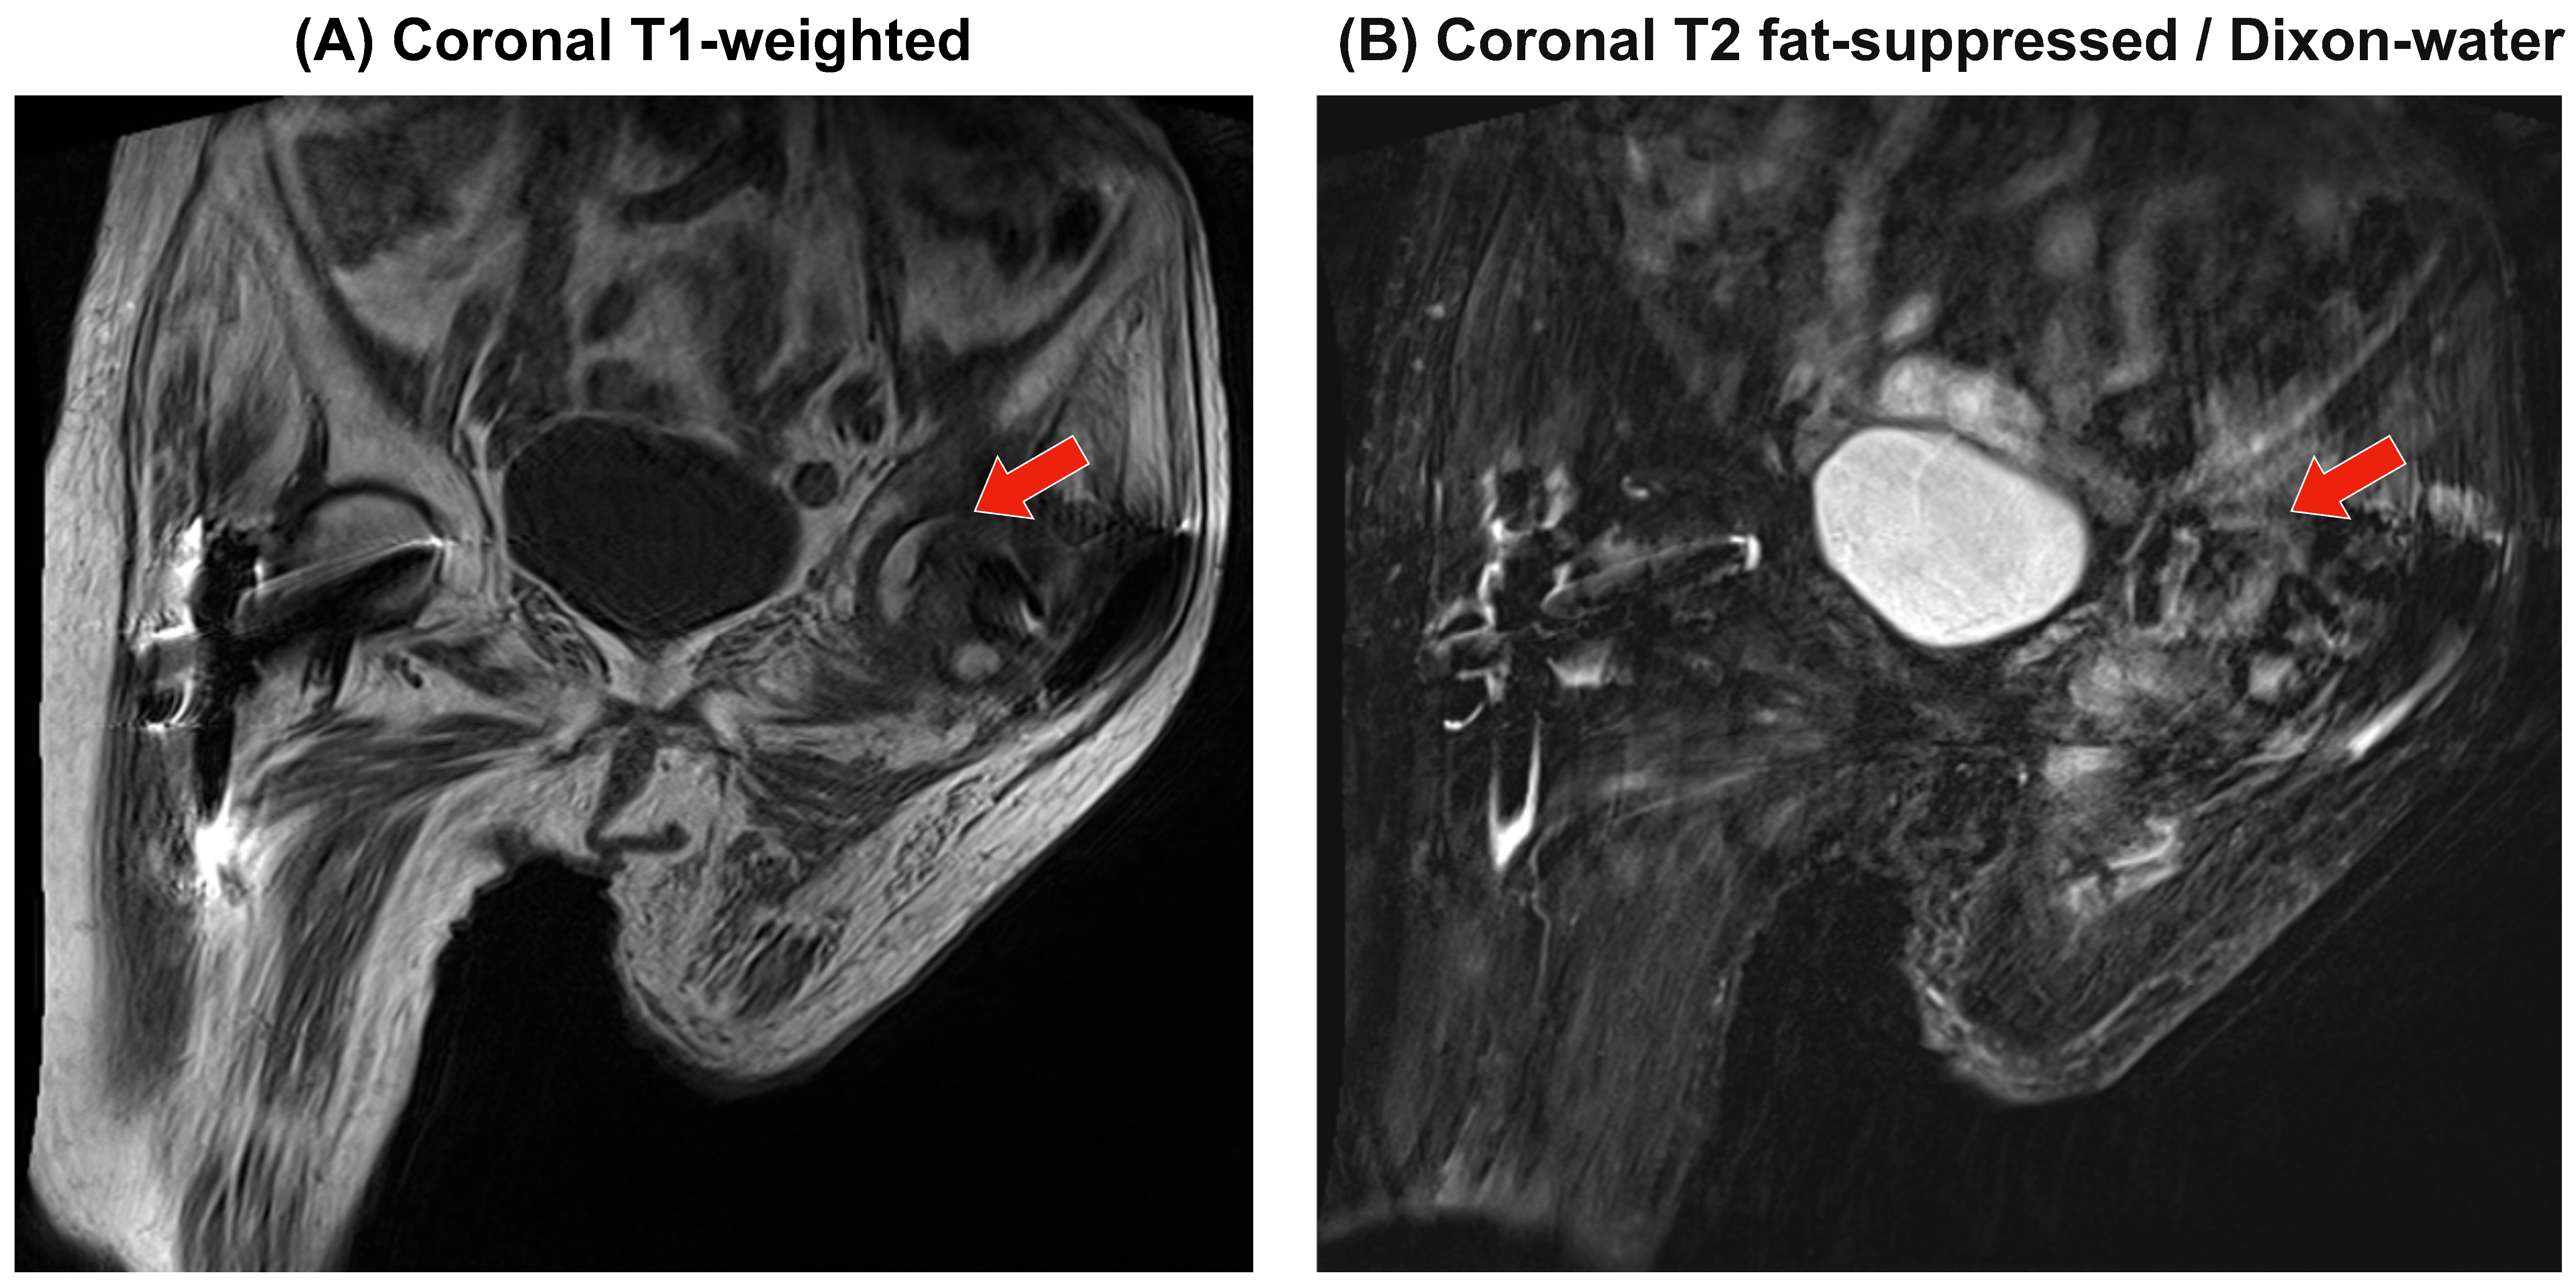

3.4. MRI at Deterioration

MRI performed at the time of pain progression did not demonstrate a definite subchondral low-signal band on T1; T2 fat-suppressed (Dixon-water) images showed a heterogeneous marrow signal without focal collapse, albeit limited by motion and constrained hip extension (Figure 5).

Figure 5. MRI of the hip: T1-weighted and T2 fat-suppressed (Dixon). Coronal T1-weighted (A) and coronal T2 fat-suppressed (Dixon water) (B) images of the affected hip are shown. No definite subchondral low-signal band was identified on T1; T2-FS demonstrated a heterogeneous marrow signal without focal collapse. The images were limited by motion artifacts and constrained hip extension. Red arrows indicate regions of interest.